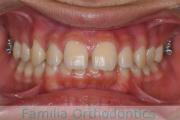

No.23V-385

- 主な症状:

- 叢生

- 年齢:

- 17歳

- 性別:

- 女性

- 抜歯部位

- 上:

- 44

- 下:

- 8448

- 主な使用装置:

- FEA 022

- 治療にかかった費用:

- 90万円

前歯のゆがみ、ズレがあるのを治したいということで来院されました。上下左右から小臼歯を抜歯して、マルチブラケット法にて治療をしました。1年8か月、20回程度の通院をしていただきました。叢生(でこぼこ、凹凸、ガタガタ)が強いため、保定をしっかりしないと後戻りのリスクがやや高いケースといえます。

- ≫治療前

-

上顎

下顎

前歯の関係など

右側

正面

左側

- ≫治療後